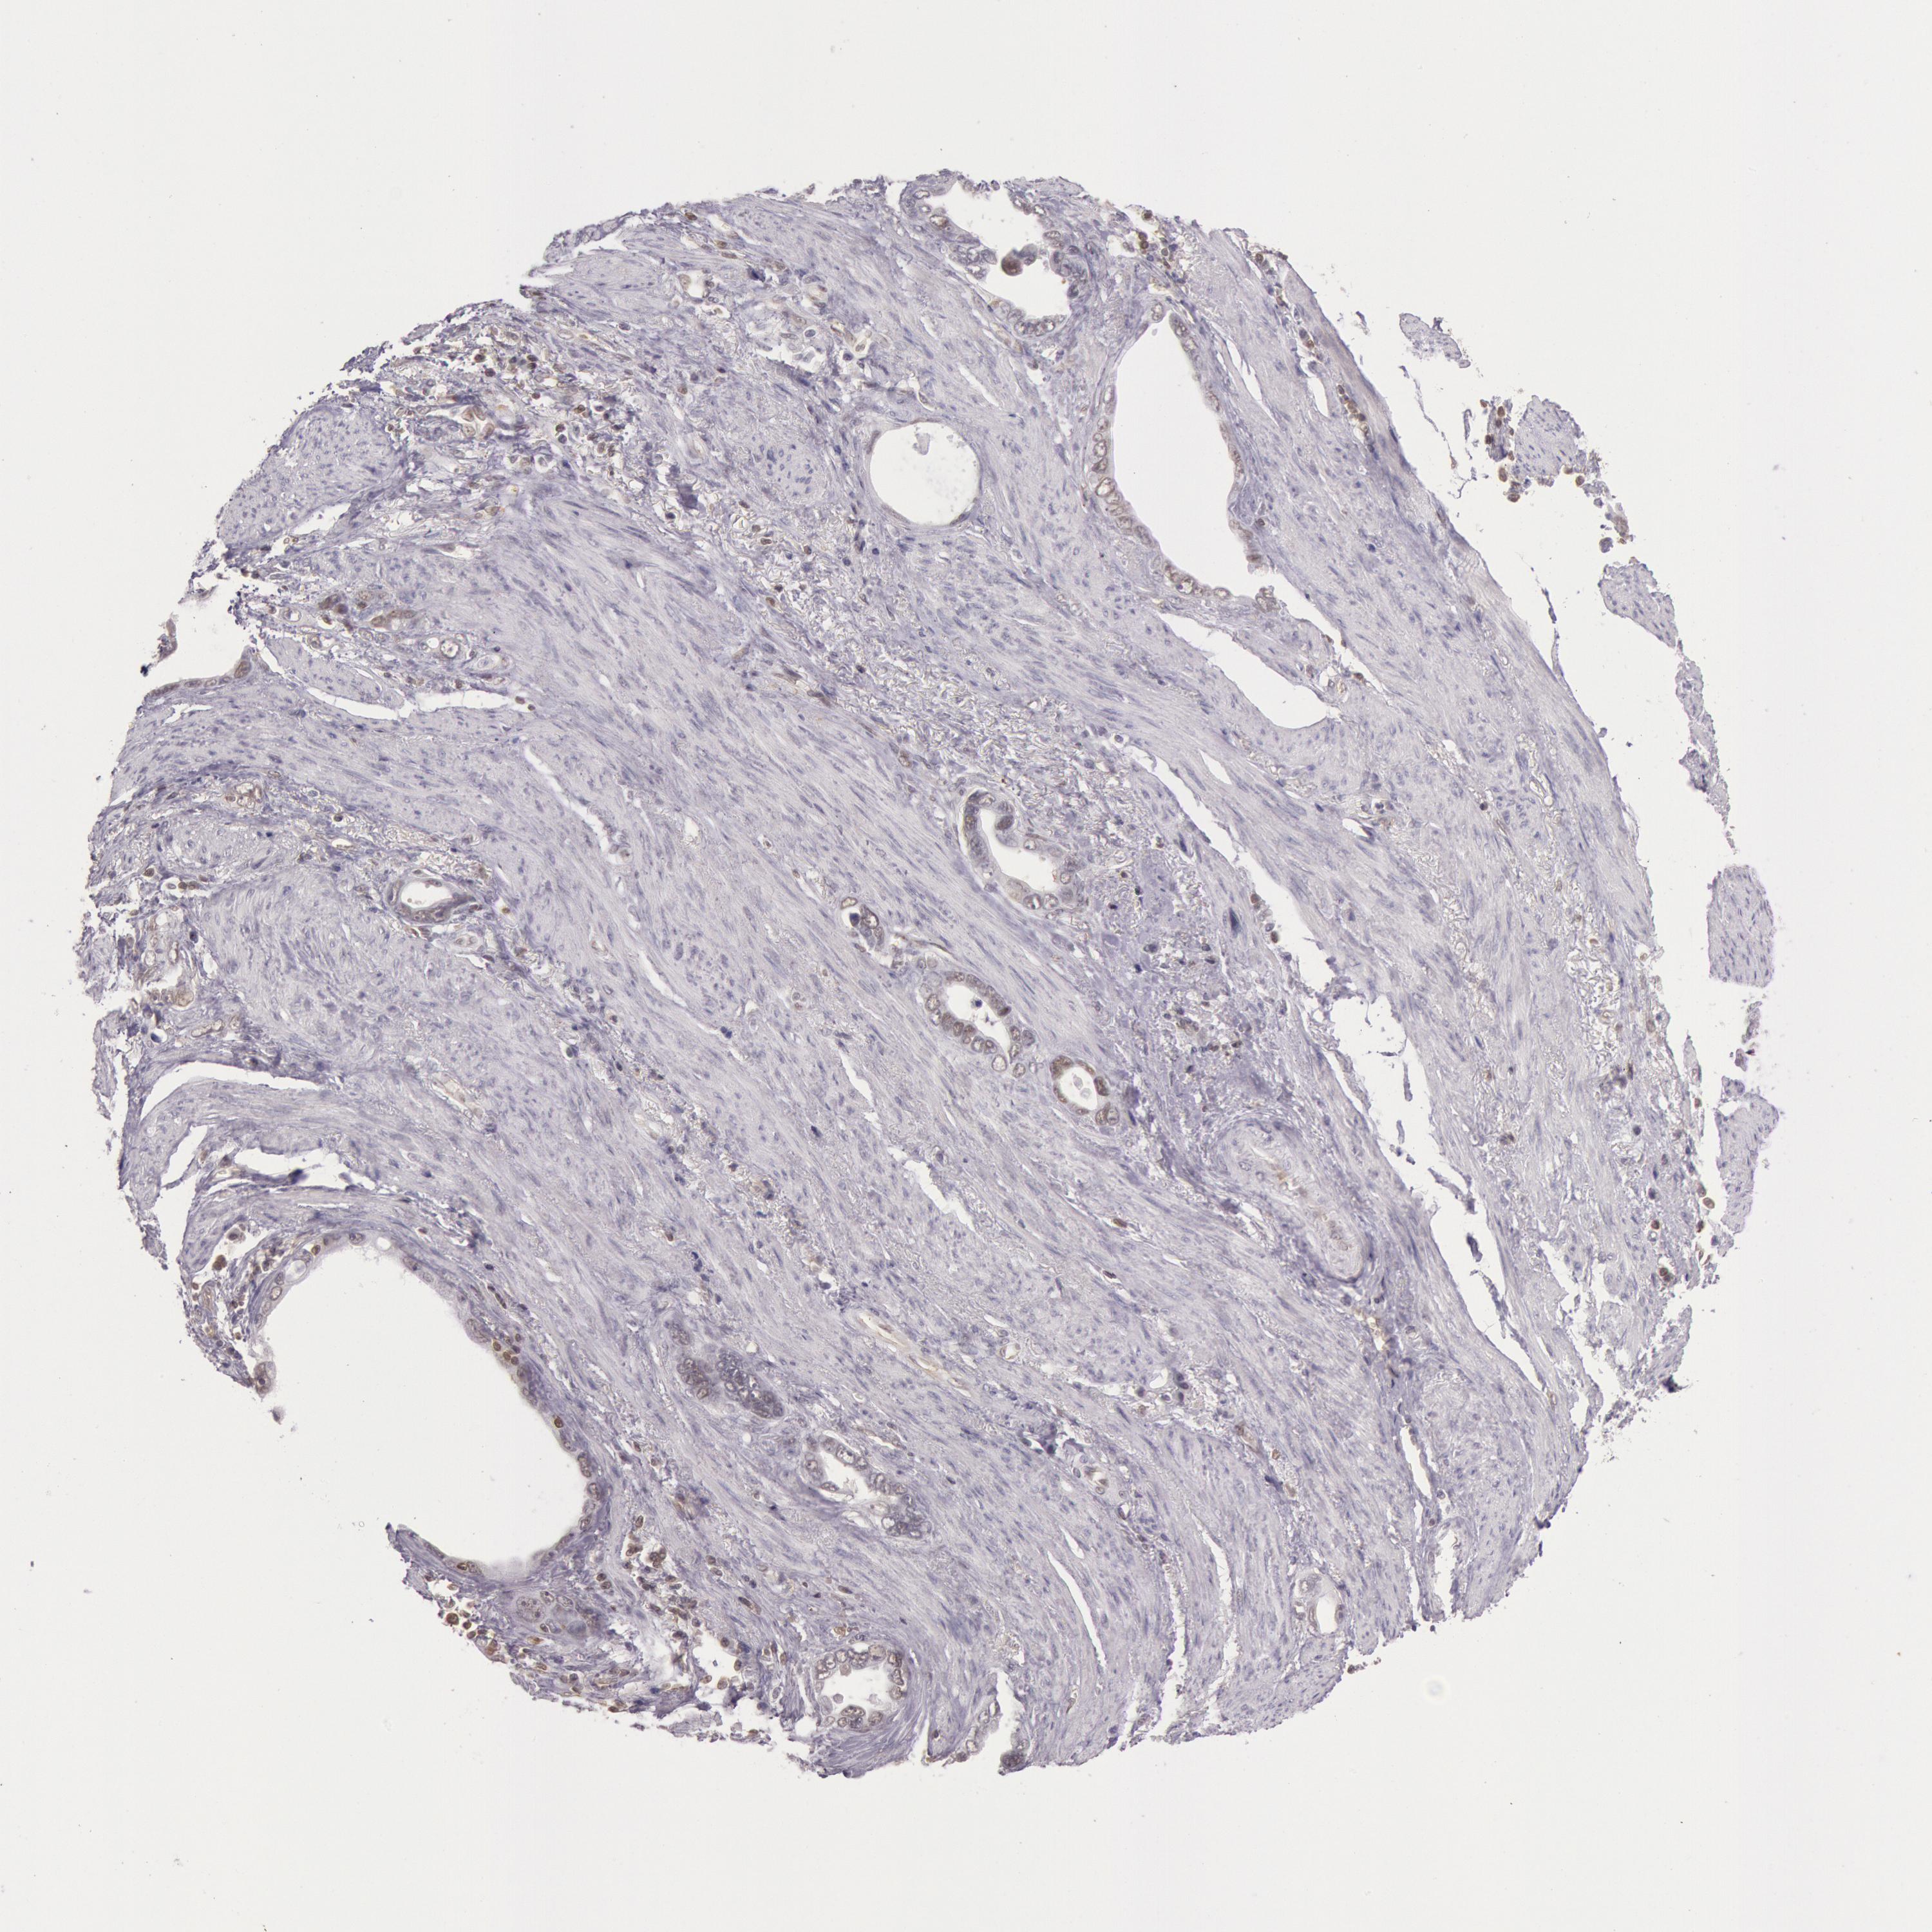

STOMACH CANCER - Protein expressioni

A mouse-over function shows sample information and annotation data. Click on an image to view it in a full screen mode. Samples can be filtered based on level of antibody staining by selecting one or several of the following categories: high, medium, low and not detected. The assay and annotation is described here.

Note that samples used for immunohistochemistry by the Human Protein Atlas do not correspond to samples in the TCGA dataset.

Antibody stainingi

Antibody staining in the annotated cell types in the current human tissue is reported as not detected, low, medium, or high, based on conventional immunohistochemistry profiling in selected tissues. This score is based on the combination of the staining intensity and fraction of stained cells.

Each image is clickable and will lead to virtual microscopy that enables deeper exploration of all samples and also displays staining intensity scores, fraction scores and subcellular localization as well as patient and tissue information for each sample.

Antibody HPA001275

Antibody CAB017442

Staining

High

Medium

Low

Not detected

Intensity

Strong

Moderate

Weak

Negative

Quantity

>75%

75%-25%

<25%

None

Location

Nuclear

Cytoplasmic/membranous

Cytoplasmic/membranous,nuclear

Adenocarcinoma, NOS

Adenocarcinoma, High grade